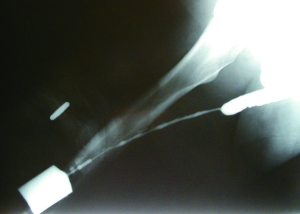

Patient positioning during retrograde urethrogram is critical. The patient should be in an oblique position (35-45 degrees) to maximize visualization of the bulbar urethra. Proper positioning can be confirmed by a closed downward oriented obturator foramen. Such a position ensures that the majority of the urethra is parallel to the radiographic film. Improper positioning will place the urethra at an angle relative to the film, and result in underestimation of stricture length (5). The penis should be placed on stretch in order to maximize complete assessment of the urethra. The use of anesthetic-impregnated lubrication can obscure the image, induce edema, and provide questionable benefit to patient comfort (6). Contrast should be visualized through the stricture and the membranous urethra to allow imaging of the urethra proximal to the stricture, in order to ensure that the full extent of urethral pathology is visualized. The importance of patient positioning is demonstrated in Figure 1.